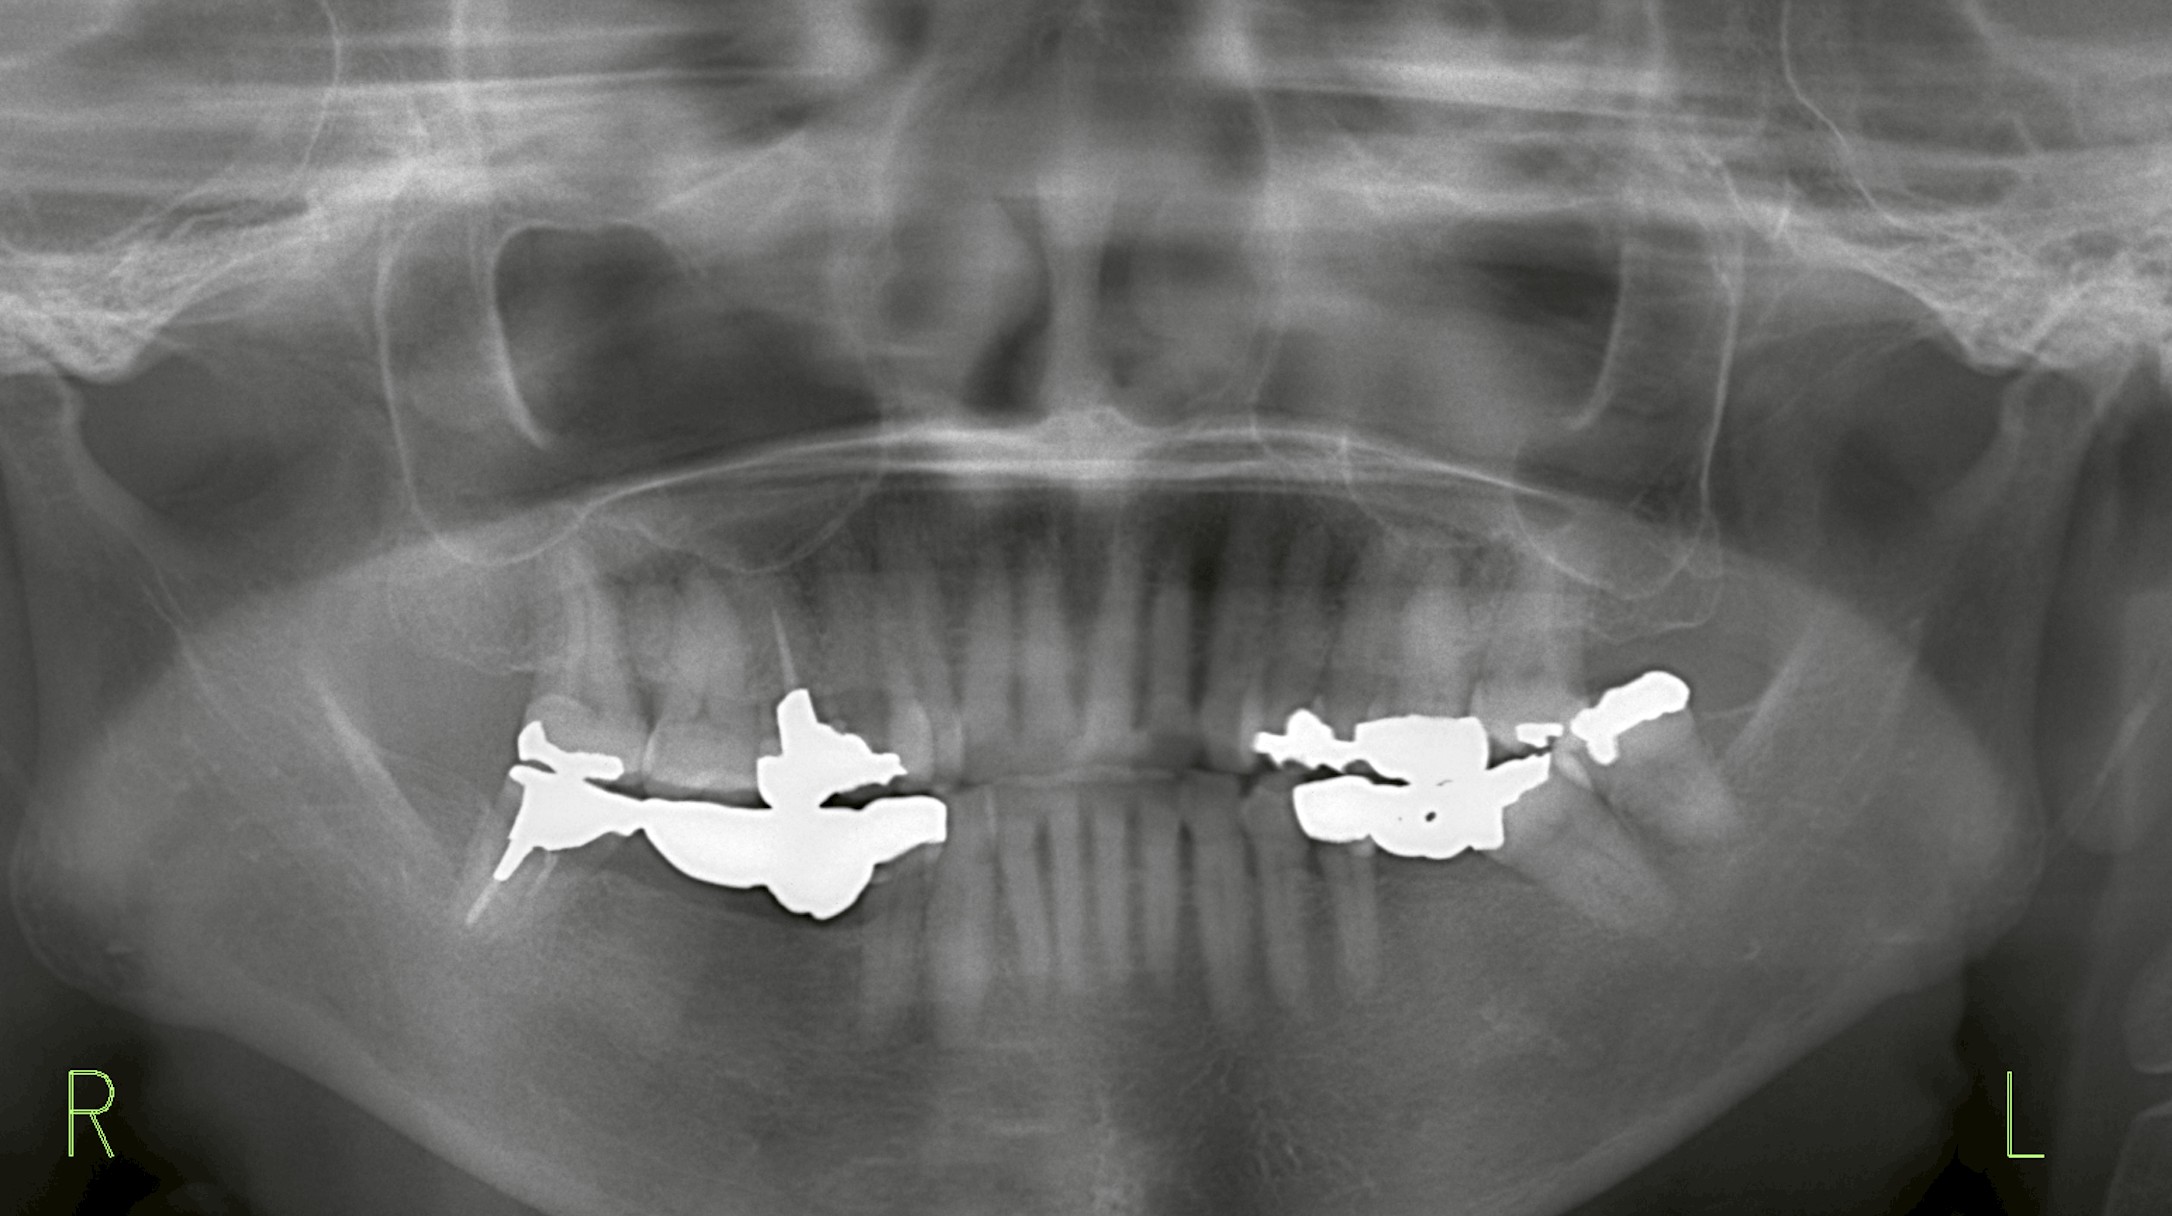

確認すると、右下に4本分のブリッジが装着されており、その一番奥の支えの歯(47部位)に破折が発生していました。

右下47を抜歯した当日に、45・46部位にインプラント埋入を行い、延長ブリッジによる補綴を計画しました。